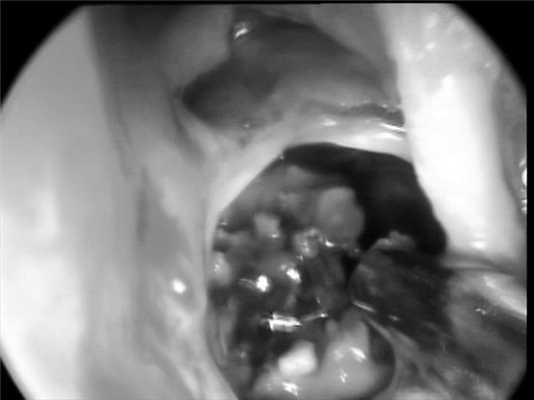

Произведена сфеноидотомия парасептальным доступом, при этом использовалась оптика ULYSS («Sopro-Comeg GmbH», Германия). Синускоп ULYSS с меняющимся углом обзора особенно удобен при операциях на клиновидной пазухе, поскольку позволяет дойти до расширенного соустья с торцевым углом обзора, а далее провести осмотр полости пазухи с помощью 45, 70 и 100° обзора. В данном случае это особенно значимо, поскольку при расширении естественного соустья и аспирации слизисто-гнойного отделяемого было визуализировано грибковое тело, движущееся маятникообразно в соответствии с пульсом пациента. Кроме того, основная масса грибкового тела располагалась ниже уровня естественного соустья. Поэтому возможность смены угла обзора, не выходя при этом из полости пазухи, позволила осмотреть латеральную стенку с выпячиванием канала зрительного нерва, зрительно-каротидное углубление, эрозированный канал внутренней сонной артерии, а также дно клиновидной пазухи. Смена угла обзора внутри клиновидной пазухи ощутимо сэкономила время операции, позволила чувствовать себя «безопаснее» в столь сложной ситуации (рис. 2). Рисунок 2. Эндофотография клиновидной пазухи больного Е. После сфеноидотомии парасептальным доступом визуализировано грибковое тело, движущееся маятникообразно в такт пульсу пациента. Заключительный клинический диагноз — грибковое тело клиновидной пазухи.